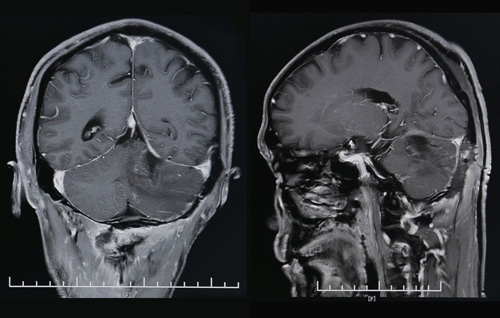

术后CT影像显示,肿瘤已经消失